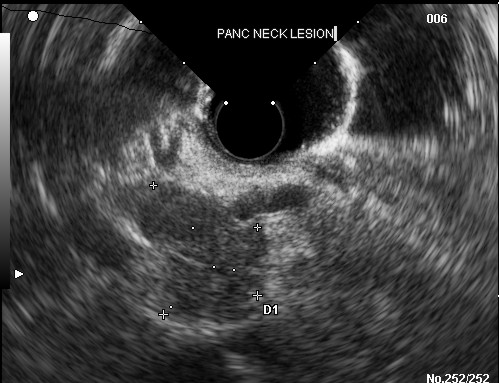

A 67-year-old female with history of metastatic carcinoid tumor presented with worsening abdominal pain, nausea, bloating, and finding of new onset ascites on computerized tomography (CT) about two weeks after endoscopic ultrasound guided fine needle aspiration at an outside facility. During the EUS, a 2.5x2.2 centimeter hypoechoic lesion (Figure 1) was seen in the neck of the pancreas. Fine needle aspiration of the mass was performed with a 25 gauge Echotip® needle (Wilson Cook, Winston-Salem, NC, USA) and a total of three passes were made. The cytological interpretation of the aspirate was consistent with well differentiated neuroendocrine tumor.

Figure 1. Endoscopic ultrasonic image of the pancreatic neck lesion. |